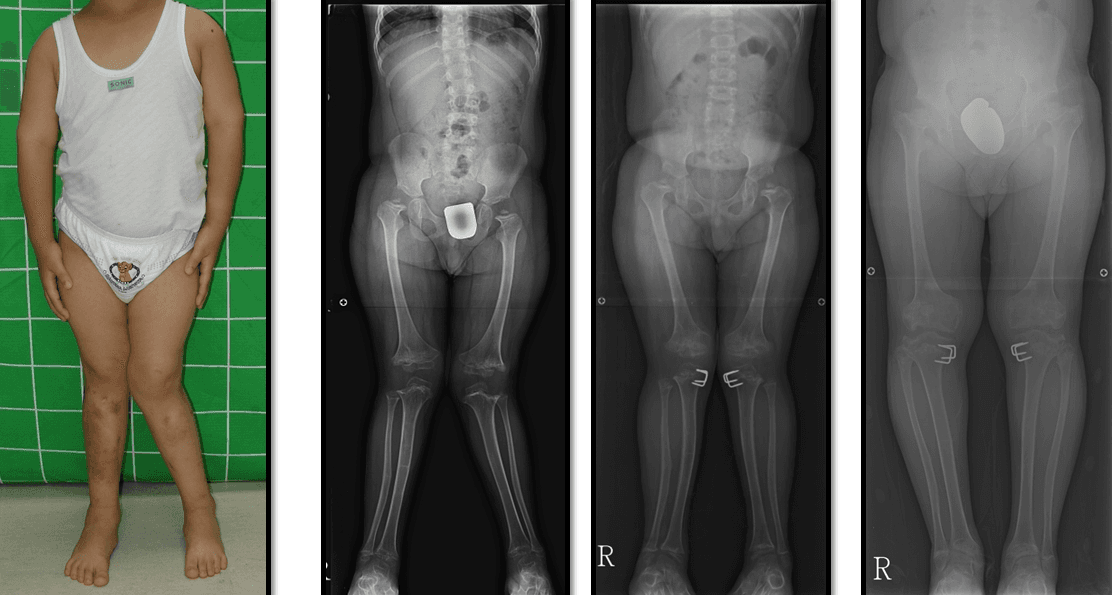

The legs were curved outwards due to multiple epiphyseal dysplasia, and they became normal leg shapes after correction surgery.

Correct valgus deformity caused by epiphyscaldisplasia, resulting normal leg shape.